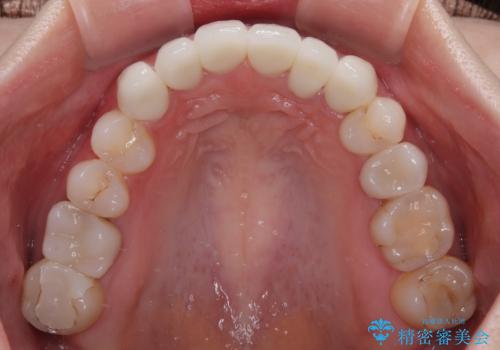

- 全体的なデコボコと、奥歯の欠損を放置した結果倒れ込んだ奥歯などを気にして来院された患者様です。

ワイヤー矯正の方が理想的な仕上がりとできる状態でしたが、上顎前歯にクラウンが装着されているため、インビザラインにて矯正治療を行うこととしました。

インビザラインのみで対応できないときにはワイヤー矯正を併用することとし、矯正治療後にはオールセラミッククラウンによる補綴治療を行うこととしました。

矯正治療自体はインビザラインで満足のいく仕上がりとなりました。

前歯は根管治療が必要となり、元々舌側に入り込んでいた左上2番目の歯は歯周外科処置により歯肉ラインを整えることとしました。

欠損部位は傾斜歯軸を起き上がらせることができたため、オールセラミッククブリッジにて補綴治療を行いました。

全顎的に満足のいく仕上がりとなりました。